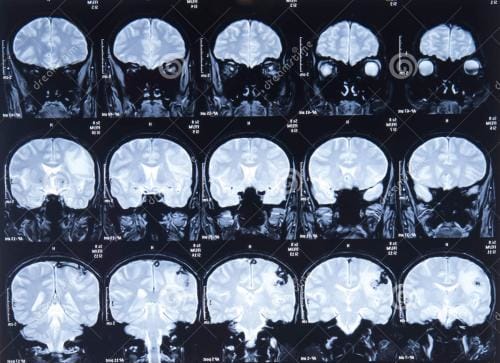

也称扫描时间,是指在临床医学MRI整个脉冲序列完成信号采集所需要的时间。在不同序列中TA 的差别很大,一幅图像的TA可以在数十毫秒(如单次激发EPI),也可以是数十分钟(如SE-T2WI 序列)。